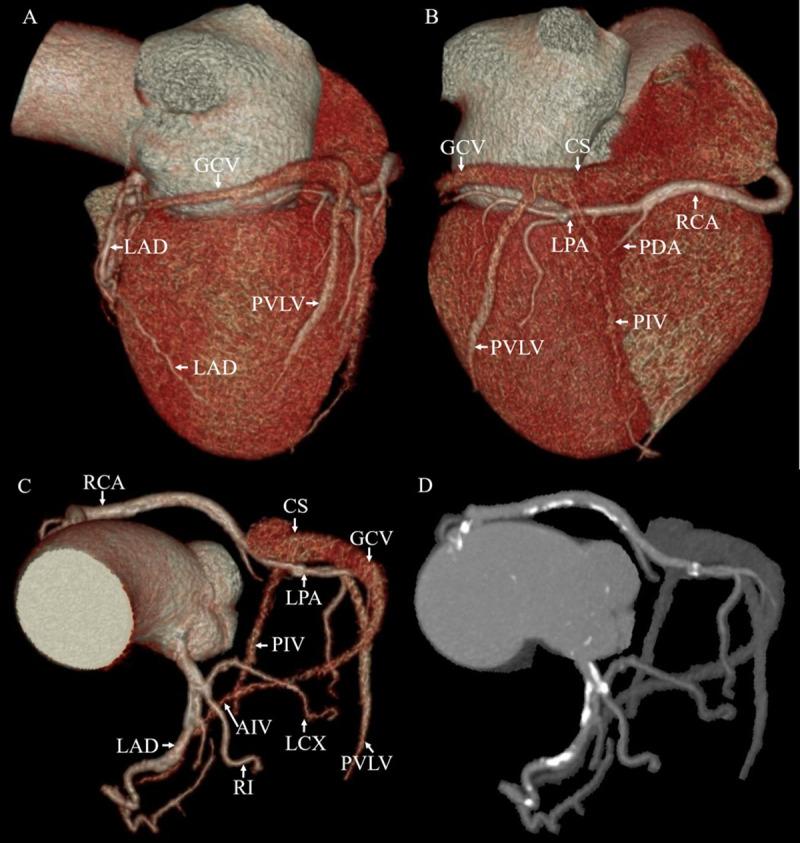

The factors that determine the anatomical variations of the coronary venous system (CVS) are poorly understood. The objective of this study was to evaluate the anatomical variations of the CVS in patients with coronary artery calcification. 196 patients underwent non-contrast CT and coronary CT angiography using 256-slice CT. All subjects were divided into four groups based on their coronary artery calcium score (CACS): 50 patients with CACS = 0 Agatston unit (AU), 52 patients with CACS = 1-100 AU, 44 patients with CACS = 101-400 AU, and 50 patients with CACS > 400 AU. The presence of the following cardiac veins was evaluated: the coronary sinus (CS), great cardiac vein (GCV), posterior interventricular vein (PIV), posterior vein of the left ventricle (PVLV), left marginal vein (LMV), anterior interventricular vein (AIV), and small cardiac vein (SCV). Vessel diameters were also measured. We found that the CS, GCV, PIV, and AIV were visualized in all patients, whereas the PVLV and LMV were identified in a certain proportion of patients: 98% and 96% in the CACS = 0 AU group, 100% and 78.8% in the CACS = 1-100 AU group, 93.2% and 77.3% in the CACS = 101-400 AU group, and 98% and 78% in the CACS > 400 AU group, respectively. The LMV was less often identified in the last three groups than in the first group (p < 0.05). The frequency of having either one PVLV or LMV was higher in the last three groups than in the first group (p < 0.05). No significant differences in vessel diameters were observed between the groups. It was concluded that patients with coronary artery calcification were less likely to have the LMV, which might hamper the left ventricular lead implantation in cardiac resynchronization therapy.

冠状动脉静脉系统(CVS)解剖变异的决定因素尚不清楚。本研究旨在评估冠状动脉钙化患者 CVS 的解剖变异。196 例患者接受了 256 层 CT 进行非对比 CT 和冠状动脉 CT 血管造影。所有患者均根据冠状动脉钙评分(CACS)分为 4 组:50 例 CACS = 0 个 Agatston 单位(AU),52 例 CACS = 1-100 AU,44 例 CACS = 101-400 AU,50 例 CACS > 400 AU。评估了以下心静脉的存在情况:冠状窦(CS)、大心静脉(GCV)、后室间静脉(PIV)、左心室后静脉(PVLV)、左缘静脉(LMV)、前室间静脉(AIV)和小心静脉(SCV)。还测量了血管直径。我们发现 CS、GCV、PIV 和 AIV 在所有患者中均可见,而 PVLV 和 LMV 在一定比例的患者中可见:CACS = 0 AU 组为 98%和 96%,CACS = 1-100 AU 组为 100%和 78.8%,CACS = 101-400 AU 组为 93.2%和 77.3%,CACS > 400 AU 组为 98%和 78%。最后三组 LMV 的检出率明显低于第一组(p < 0.05)。后三组中同时存在 PVLV 或 LMV 的频率明显高于第一组(p < 0.05)。各组之间血管直径无明显差异。结论:冠状动脉钙化患者更有可能没有 LMV,这可能会妨碍心脏再同步治疗中左心室导线的植入。